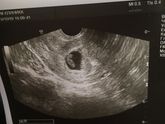

19 октября 2019 15:23 Сходила на узи))...все у нас отлично, сердечко бьется? свд-17мм ктр-7,7мм соответствует 6нед.5дней